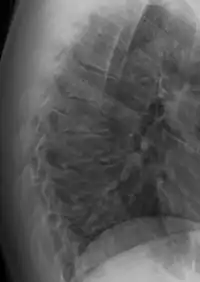

Scheuermann's disease

Scheuermann's disease is a self-limiting skeletal disorder of childhood. Scheuermann's disease describes a condition where the vertebrae grow unevenly with respect to the sagittal plane; that is, the posterior angle is often greater than the anterior. This uneven growth results in the signature "wedging" shape of the vertebrae, causing kyphosis. It is named after Danish surgeon Holger Scheuermann.[3][4][5]

| Scheuermann's disease on lateral Xray of the T spine | |

Diagnosis is typically by medical imaging. The degree of kyphosis can be measured by Cobb's angle and sagittal balance.